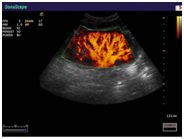

Компания SonoScape уделила особое внимание допплеровским режимам и является экспертом в своем классе, что позволяет с легкостью, но в то же время с уникальной точностью проводить исследования с постановкой наиболее точного диагноза.

Ультразвуковые исследования, доплеровское сканирование сосудов в Медицинском центре «АКВА МЕД МАРИН» выполняется при помощи первого и единственного аппарата в Керчи SonoScape S40Exp (экспертного класса, который оснащен множеством новейших функций, многократно улучшающих качество и информативность УЗИ-исследования).